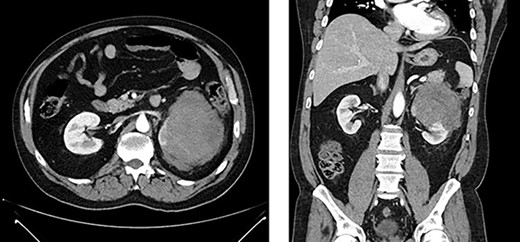

Left renal mass measuring 11 × 9 × 7cm in transverse (left) and coronal (right) planes.

A 52-year-old, previously healthy, Caucasian male presented to the emergency department (ED) with chief complaints of gross hematuria, abdominal pain, vomiting, diarrhea and left flank pain for 3 days. He had neither family history of cancer nor history of exposure to ionizing radiation, arsenic, thorium dioxide or vinyl chloride. He reported exposure to chemical tankers 10 years prior and had recent occupational exposure to paint-thinning agents. Urinalysis on admission showed large blood with later cytology significant for atypical epithelioid cells concerning for neoplasm of the kidney or bladder. Subsequent contrast-enhancedcomputed tomography (CT) of the abdomen revealed an 11-cm left renal mass, 2-cm para-aortic lymphadenopathy and possible invasion of the tail of the pancreas (Fig. 1). He was then referred to urology for evaluation and to discuss treatment options.